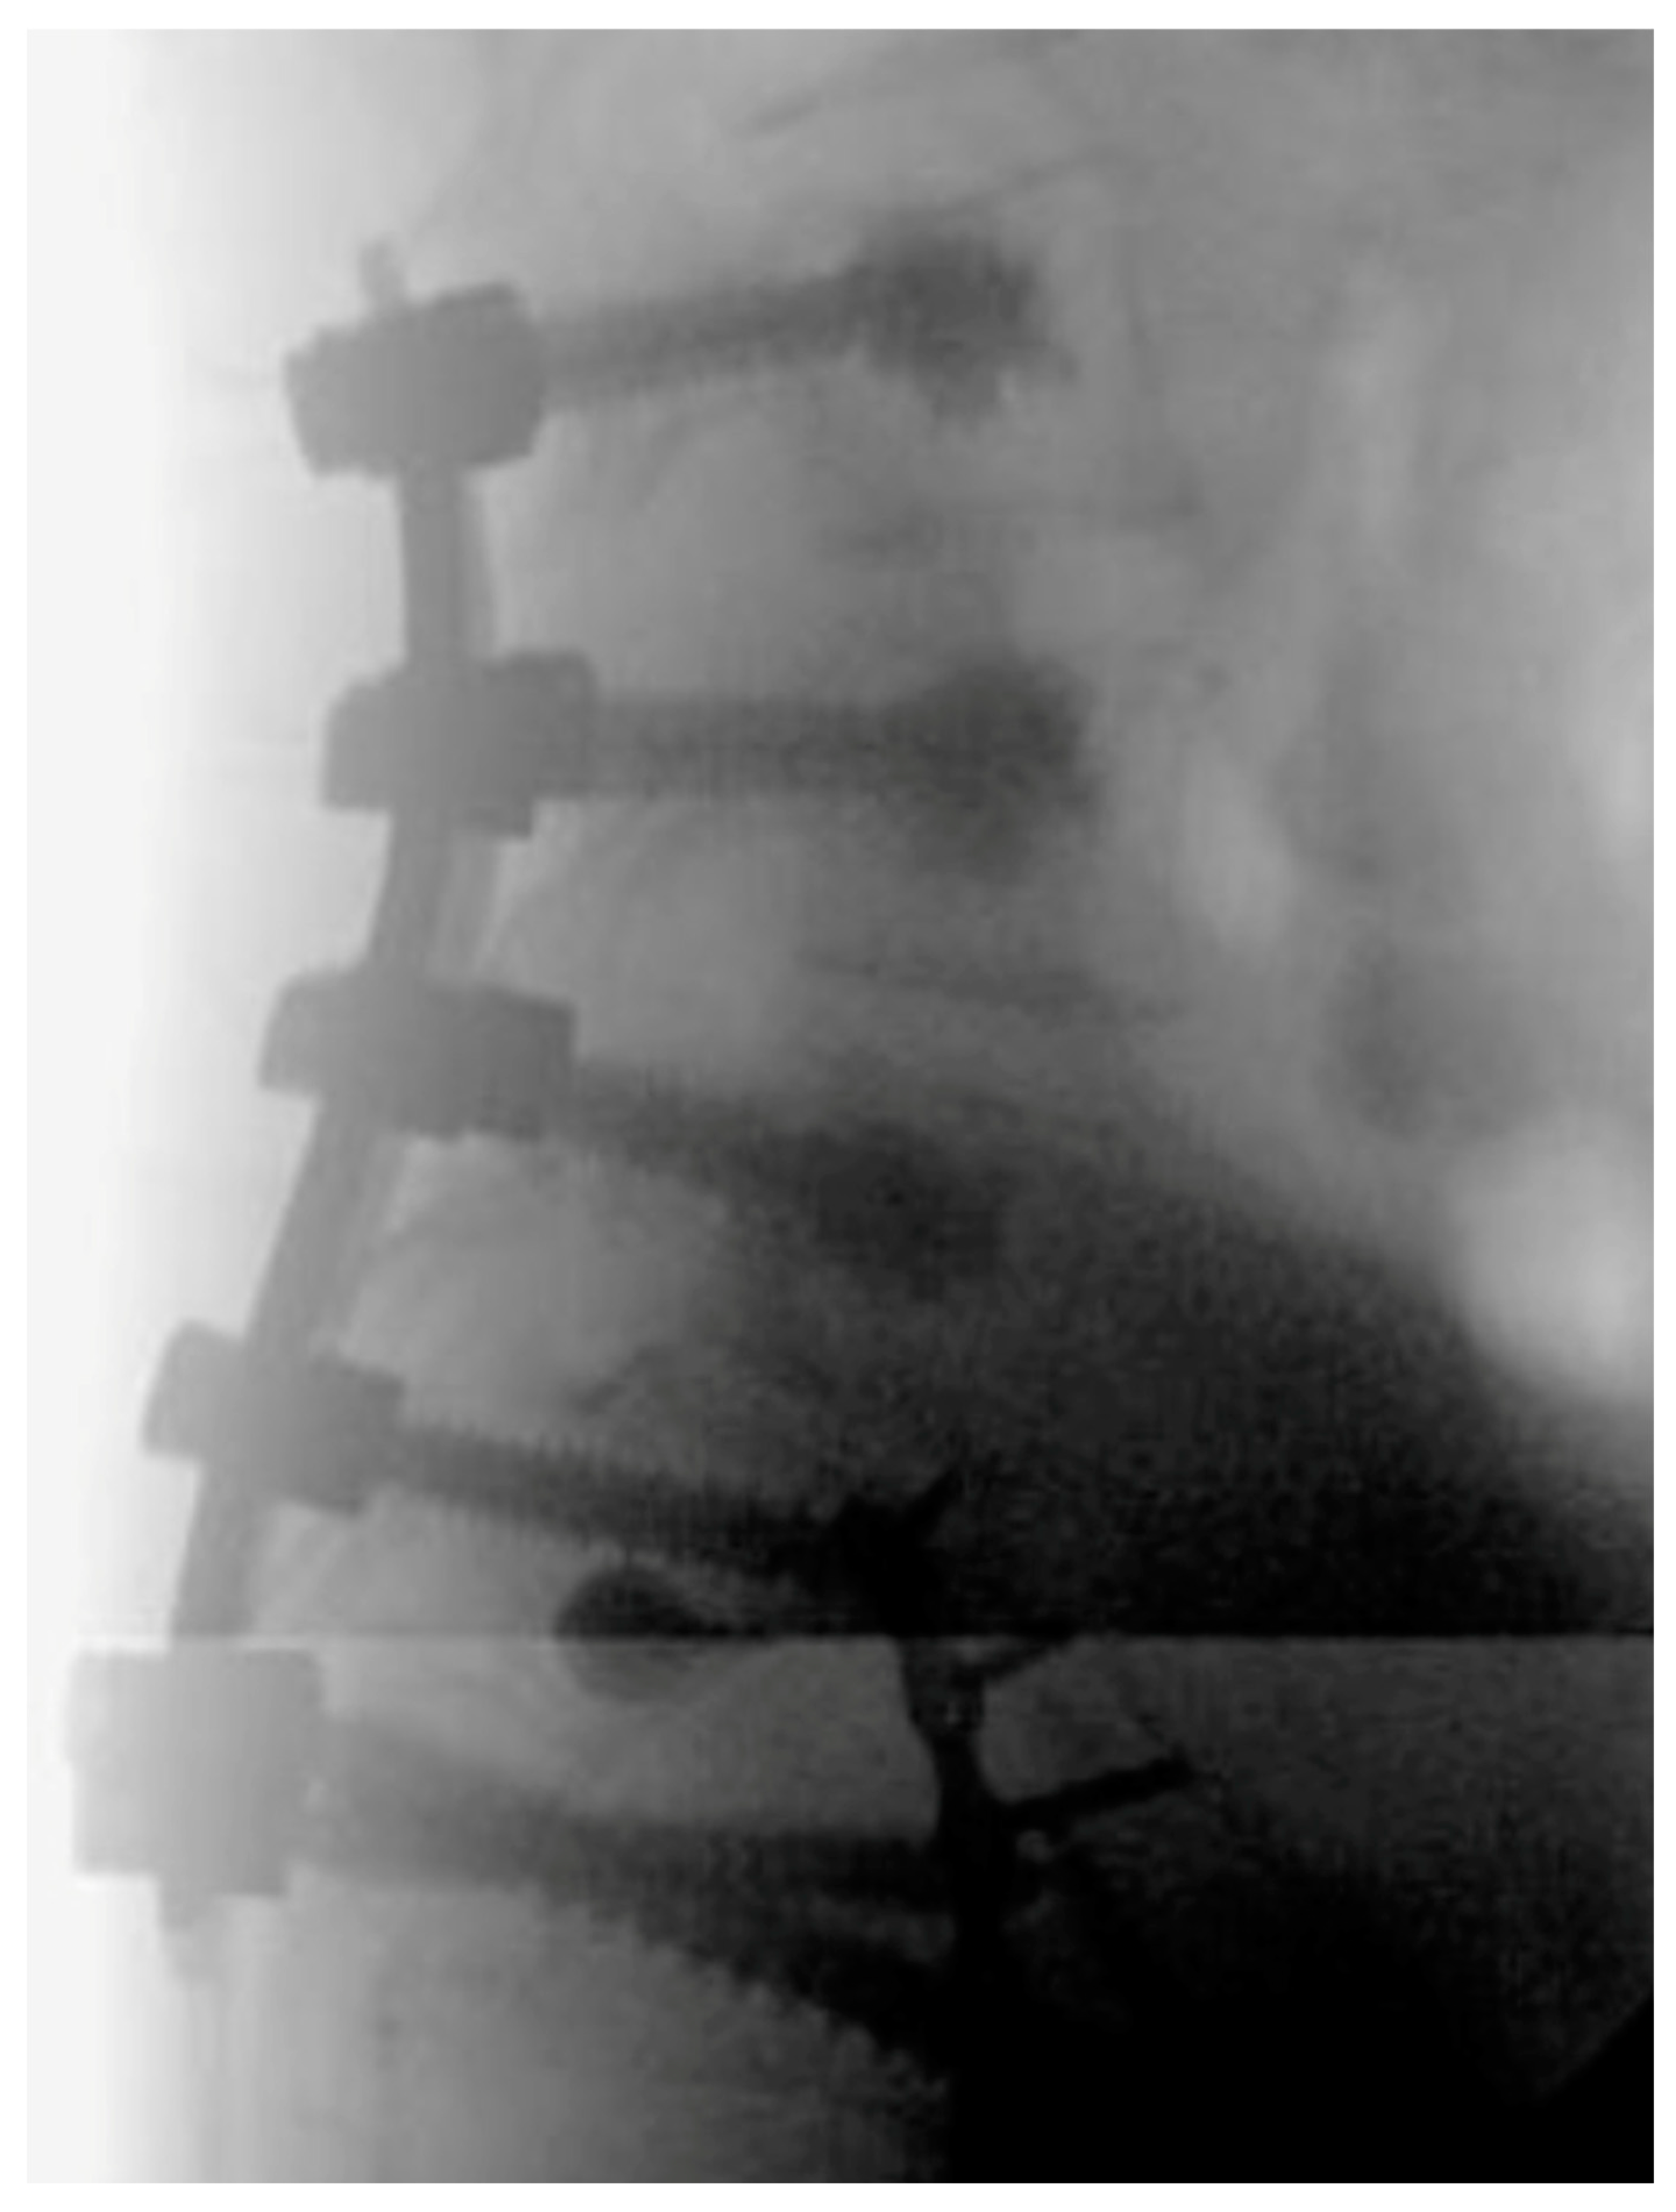

5. Techniques and Considerations in Spinopelvic Fixation: Sequence, Reduction, and Avoiding Complications

6. Spinopelvic Fixation Percutaneous Technique

7. Tran-Sacral Percutaneous Technique